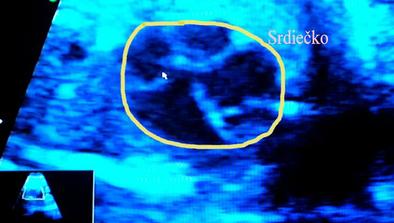

@monika0001 juj dufam ze ste v poriadku takze poradna jooj zasa si popozeras to nadherne srdiecko ze 🙂 ja viem je to nadhera fakt 🙂

@l123456 - tomu ver. asi ani spať nebudem 😀